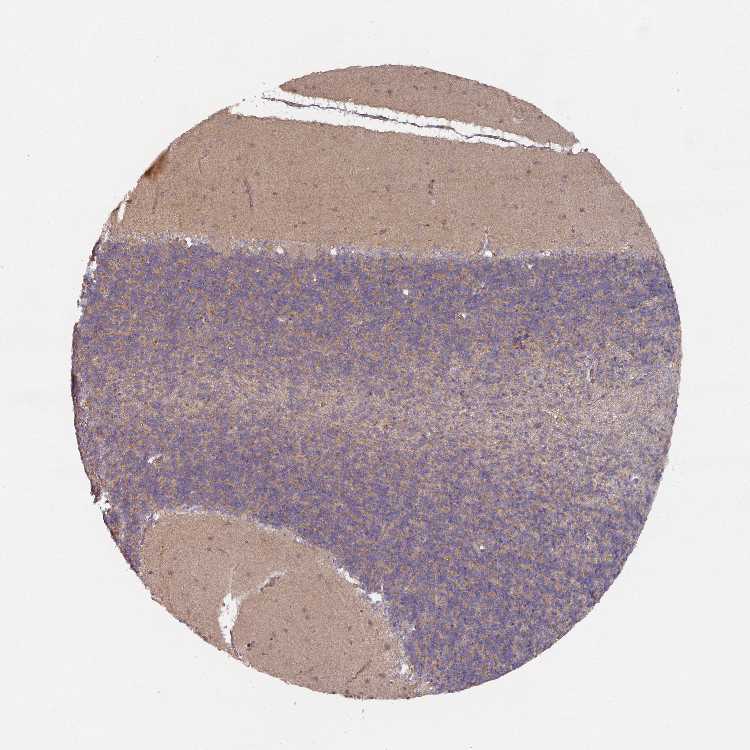

CEREBELLUM - Antibody stainingi

Antibody staining in the annotated cell types in the current human tissue is reported as not detected, low, medium, or high, based on conventional immunohistochemistry profiling in selected tissues. This score is based on the combination of the staining intensity and fraction of stained cells.

Each image is clickable and will lead to virtual microscopy that enables deeper exploration of all samples and also displays staining intensity scores, fraction scores and subcellular localization as well as patient and tissue information for each sample.

Antibody HPA052426Antibody HPA052428Antibody HPA061371

Purkinje cells MediumMediumLow

Cells in granular layer Not detectedHighNot detected

Cells in molecular layer Not detectedLowNot detected